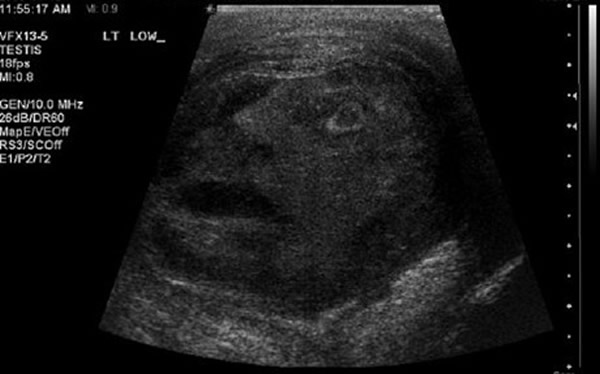

接受超音波检查的睾丸,照片中赫然出一张「人脸」!

事实上,超音波很容易就照出些有趣的东西,先前21岁妈妈史都华在产检时,照片里就出现一只「鸭子」,坐在宝宝的身上;加拿大一名患者在进行睾丸超音波检查时,也看见自己的「宝贝」上冒出一张人脸。(神秘的地球uux.cn)